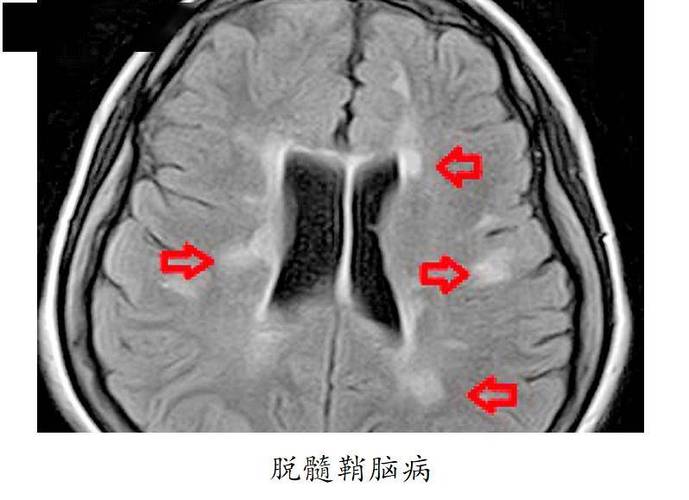

在临床上,当头颅MRI(磁共振)发现患者有广泛的脑白质脱髓鞘(尤其是脑白质疏松)时,医生会高度警惕,这表明患者的脑血管已经出现了严重的病变,未来发生脑梗、认知障碍甚至痴呆的风险非常高,脑白质脱髓鞘可以看作是脑血管健康状况的一个“晴雨表”和“预警信号”。